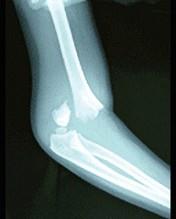

问题 图示骨折,最常见的并发症是 ( )

选项 A、骨折局部感染 B、脂肪栓塞 C、损伤性休克 D、血管神经损伤 E、肱骨下端缺血性坏死

答案 D